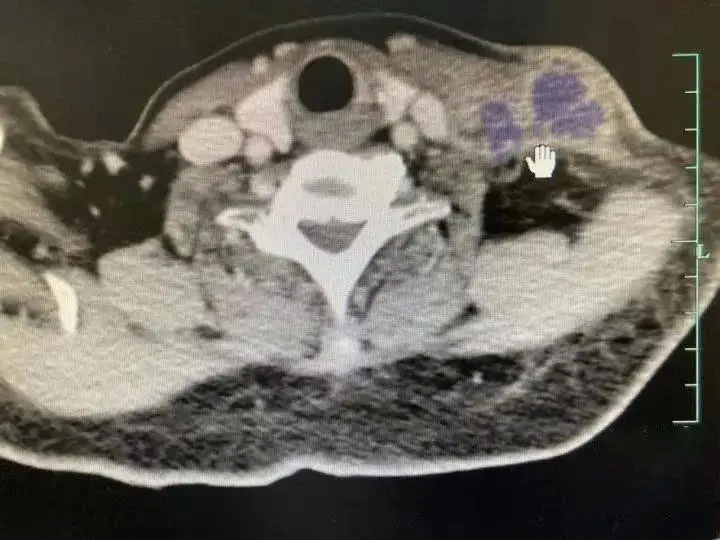

陈阿姨的CT报告结果(图源:浙医在线)